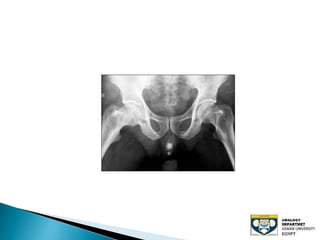

The document discusses urinary tract stones, detailing their types, causes, symptoms, and diagnostic methods. It highlights the risk factors such as infections and obstructions, with men being more commonly affected. Treatment options include various surgical methods, particularly for managing bladder outflow obstruction and lithiasis.